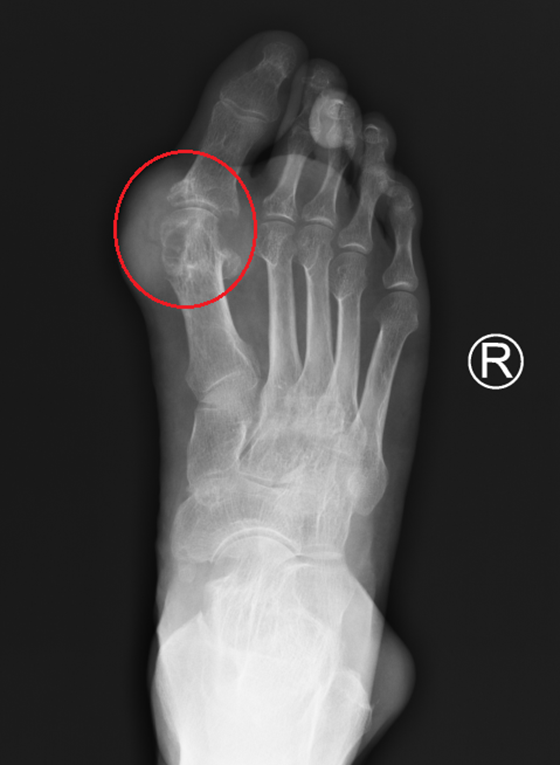

25岁年轻小伙杨某,本该是青春恣意的年纪,最近却饱受关节痛的折磨。自他15岁起关节肿痛彻底改变了他的生活。刚开始只是两只脚的大拇指又红又肿,摸上去特别烫,还非常疼痛,像有人拿刀...